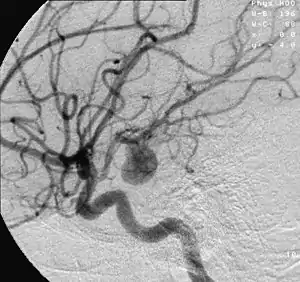

- Focal cerebral ischemia – A stroke occurring in a localized area that can either be acute or transient. This may be due to a variety of medical conditions such as an aneurysm that causes a hemorrhagic stroke, or an occlusion occurring in the affected blood vessels due to a thrombus (thrombotic stroke) or embolus (embolic stroke).[21] Focal cerebral ischemia constitutes a large majority of the clinical cases in stroke pathology with the infarct usually occurring in the middle cerebral artery (MCA).[22]